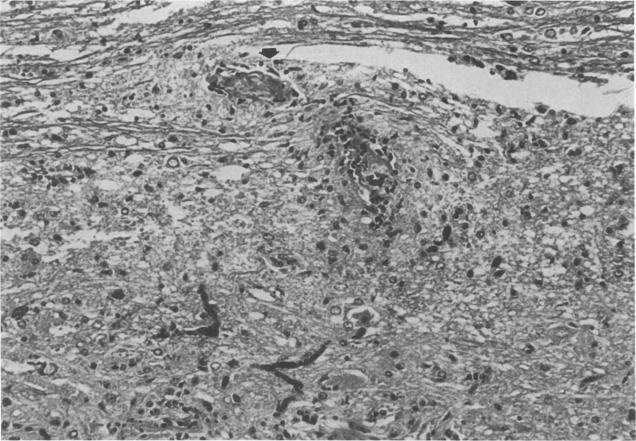

Bipiperidyl mustard and a neurotoxic triamine are known to cause edematous and/or necrotizing lesions in particular areas of hypothalamus and dorsal medulla but not in spinal cord. Experimental allergic encephalomyelitis (EAR) causes widespread inflammatory lesions that are especially numerous in spinal cord. When the chemical toxicants were administered to rats during the acute phase of EAE, mortality was increased. This was due to a specific interaction between EAE and chemical toxicants leading to the development of necrotizing vasculitis and parenchymal necrosis near EAE lesions in spinal cord or brain. The interaction decreased as the EAE lesions healed. Another neurotoxic chemical, dipiperidinoethane, did not produce this phenomenon. These effects of EAE are probably related to damage to the vessel walls and the blood-brain barrier. The present work may increase the versatility of EAE as a model for multiple sclerosis if the EAE lesions can be enlarged progressively by repeated exposures to the toxicant.

已知联哌啶基芥子气和一种神经毒性三胺会在下丘脑和延髓的特定区域引起水肿性和/或坏死性病变,但不会在脊髓中引起此类病变。实验性变应性脑脊髓炎(EAE)会导致广泛的炎性病变,这些病变在脊髓中尤其多见。当在EAE急性期给大鼠施用化学毒物时,死亡率会增加。这是由于EAE与化学毒物之间的特定相互作用导致脊髓或脑内EAE病变附近出现坏死性血管炎和实质坏死。随着EAE病变愈合,这种相互作用会减弱。另一种神经毒性化学物质二哌啶基乙烷不会产生这种现象。EAE的这些效应可能与血管壁和血脑屏障受损有关。如果通过反复接触毒物可以使EAE病变逐渐扩大,那么目前的研究工作可能会增加EAE作为多发性硬化症模型的通用性。